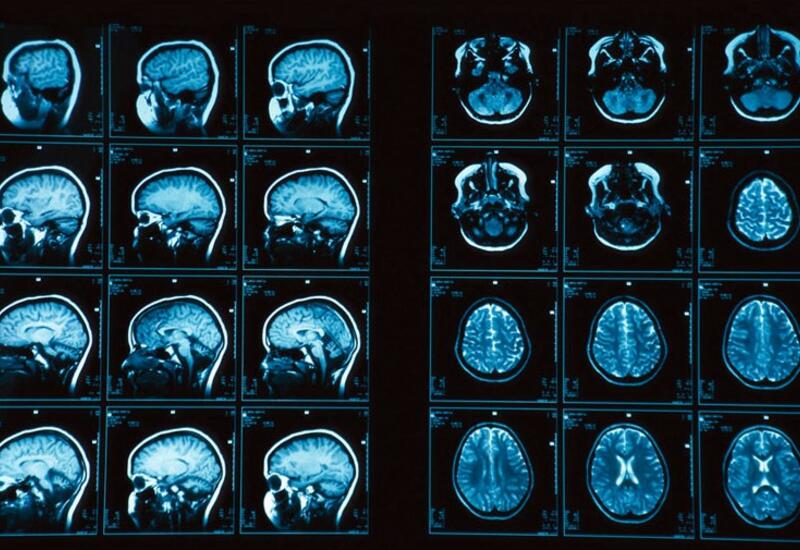

МРТ позволило увидеть признаки мигрени в мозгу человека

Ученые смогли увидеть вызванные мигренью изменения в мозгу с помощью МРТ. Об этом сообщает пресс-служба Радиологического общества Северной Америки, передает Day.Az со ссылкой на Gazeta.ru.

"У людей с хронической и эпизодической мигренью без ауры наблюдаются значительные изменения в периваскулярных пространствах мозга, в полуовальном центре", - заявляют медики. Это удалось выяснить с помощью МРТ с полем 7 тесла, в исследовании приняли участие 10 человек с хронической мигренью, 10 человек с эпизодической мигренью без ауры и пять здоровых людей того же возраста.

Периваскулярные пространства представляют собой заполненные жидкостью среды, окружающие кровеносные сосуды головного мозга. Статистический анализ показал, что у страдающих от мигрени людей расширенные периваскулярные пространств встречались гораздо чаще, чем у здоровых.

Ученые предполагают, что обнаруженные изменения связаны с проблемами лимфатической системы головного мозга. Однако неясно, является ли это следствием или причиной мигрени. Авторы работы надеются, что их исследование в итоге поможет лечить это заболевание.